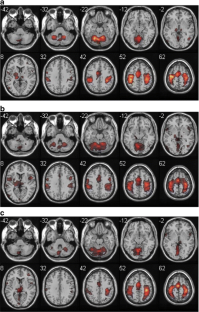

Restoration of motor function following stroke involves reorganization of motor output through intact pathways, with compensatory brain activity likely variable by task. One class of motor tasks, those involved in self-care, is particularly important in stroke rehabilitation. Identifying the brain areas that are engaged in self-care and how they reorganize after stroke may enable development of more effective rehabilitation strategies. We piloted a paradigm for functional MRI assessment of self-care activity. In two groups, young adults and older adults, two self-care tasks (buttoning and zipping) produce activation similar to a bimanual tapping task, with bilateral activation of primary and secondary motor cortices, primary sensory cortex, and cerebellum. Quantitative differences include more activation of sensorimotor cortex and cerebellum in buttoning than bimanual tapping. Pilot subjects with stroke showed greater superior parietal activity across tasks than controls, potentially representing an increased need for sensorimotor integration to perform motor tasks.

Fig. 2